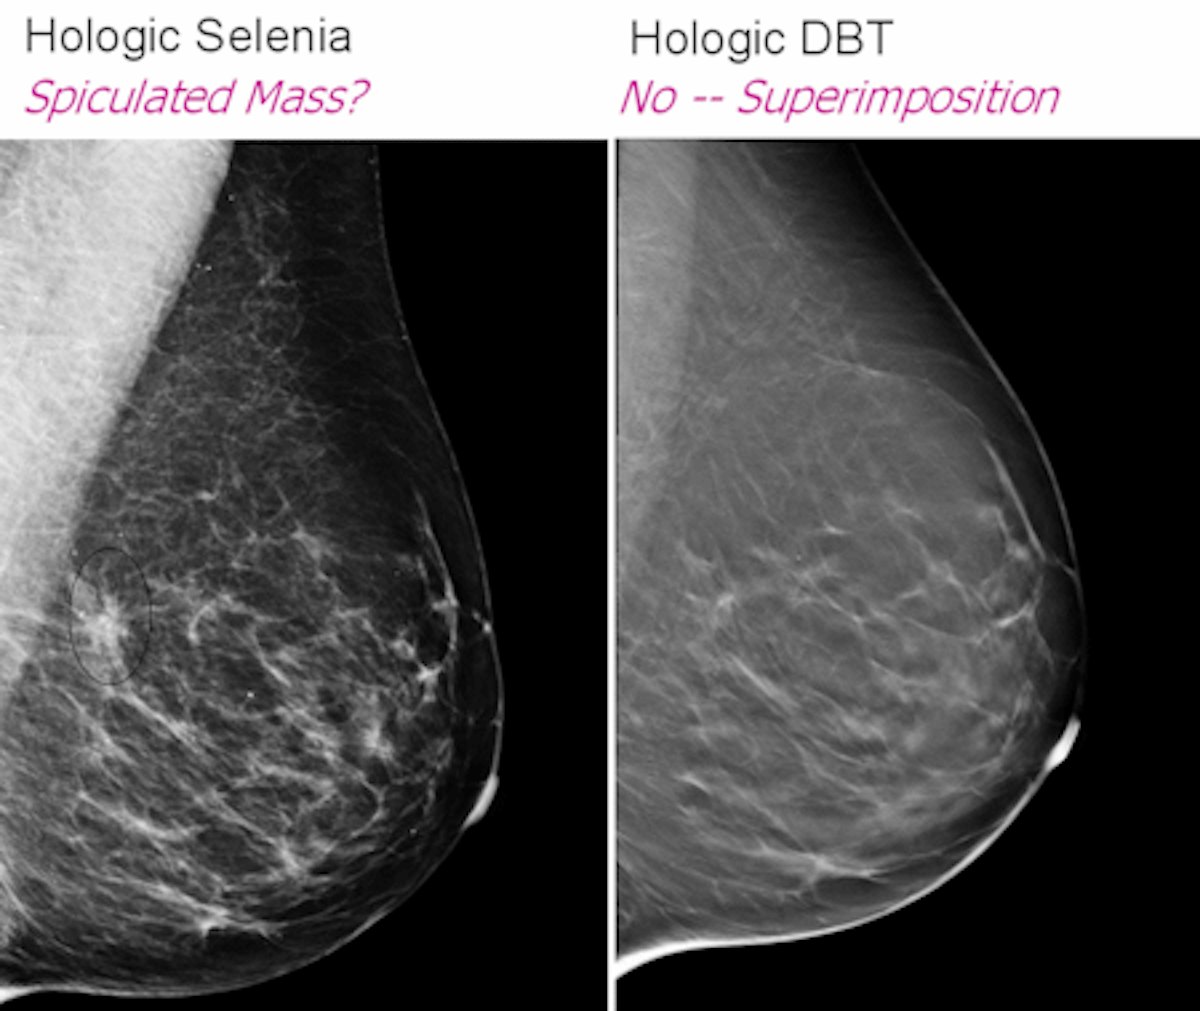

Diagnostic Imaging: Breast: 9781931884730: Medicine & Health。Diagnostic Imaging: Breast: 9780323548120: Medicine & Health。Expert 2nd Opinion Breast Imaging Consultations。マンモグラフィーや超音波などの診断技術を網羅した、拡大改訂版の医学書。。Breast Imaging: Expert Radiology Series: 9781416051992: Medicine。- 書籍名: Diagnostic Breast Imaging- 著者: Sylvia H. Hewayng-Köbrunner, D. David Dershaw, Ingrid Scherer- 版: 第2版, 拡大改訂版- 出版社: Thieme- 内容: マンモグラフィー、超音波、磁気共鳴画像、介入手技に関する情報ご覧いただきありがとうございます。図解・咬合採得 隔月刊「補綴臨床」別冊